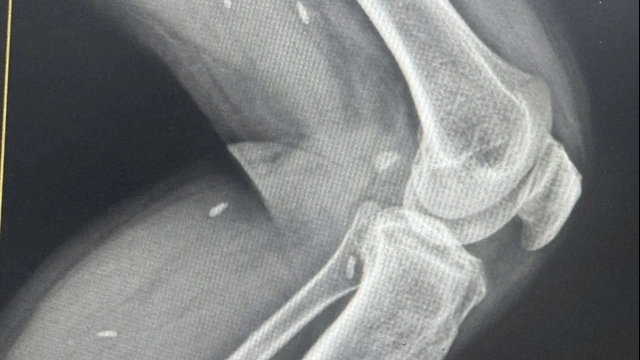

| Một bệnh nhân bị hoại tử nhiễm trùng bàn tay do rắn hổ mang cắn hiện đang được điều trị tại Trung tâm Chống độc (Ảnh: Bệnh viện cung cấp) |

Hậu quả các trường hợp rắn độc cắn là tổn thương vùng bị cắn như đau, sưng nề, hoại tử, nhiễm trùng, dễ dẫn tới sẹo, tàn phế, thậm chí tử vong. Các loài rắn như: Cạp nong, cạp nia, hổ chúa, hổ mang có thể gây liệt dẫn tới suy hô hấp và tử vong nếu không được cấp cứu kịp thời. Các loài rắn lục gây rối loạn đông máu dẫn tới chảy máu,…